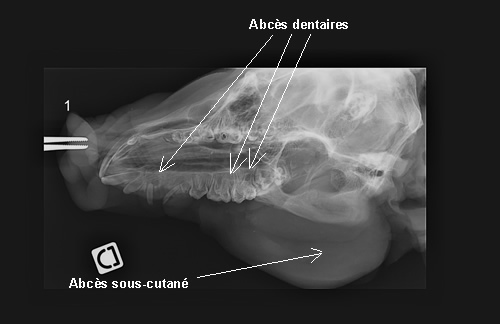

Deux têtes de porcelets sont prélevées à 4 (tête n°2 : suros) et 8 (tête n°1 : abcès sous cutané joue droite) semaines d’âge. Elles sont autopsiées à l’Ecole Nationale Vétérinaire de Nantes (ENVN).

Les têtes sont sciées horizontalement pour séparer les maxillaires afin de réaliser des radiographies sans superposition d’images.

Sur le porc n°1 : abcès sous-cutané et dentaires (incisive I3 et prémolaires PM 2 et 3)

Sur le porc n°2 : pas d’anomalie relevée à la radiographie.

Sur le porc n°1: l’abcès sous-cutané ne présente pas de fistule. Une coupe transversale du groin au niveau de l’incisive I3 permet de visualiser l’abcès dentaire.